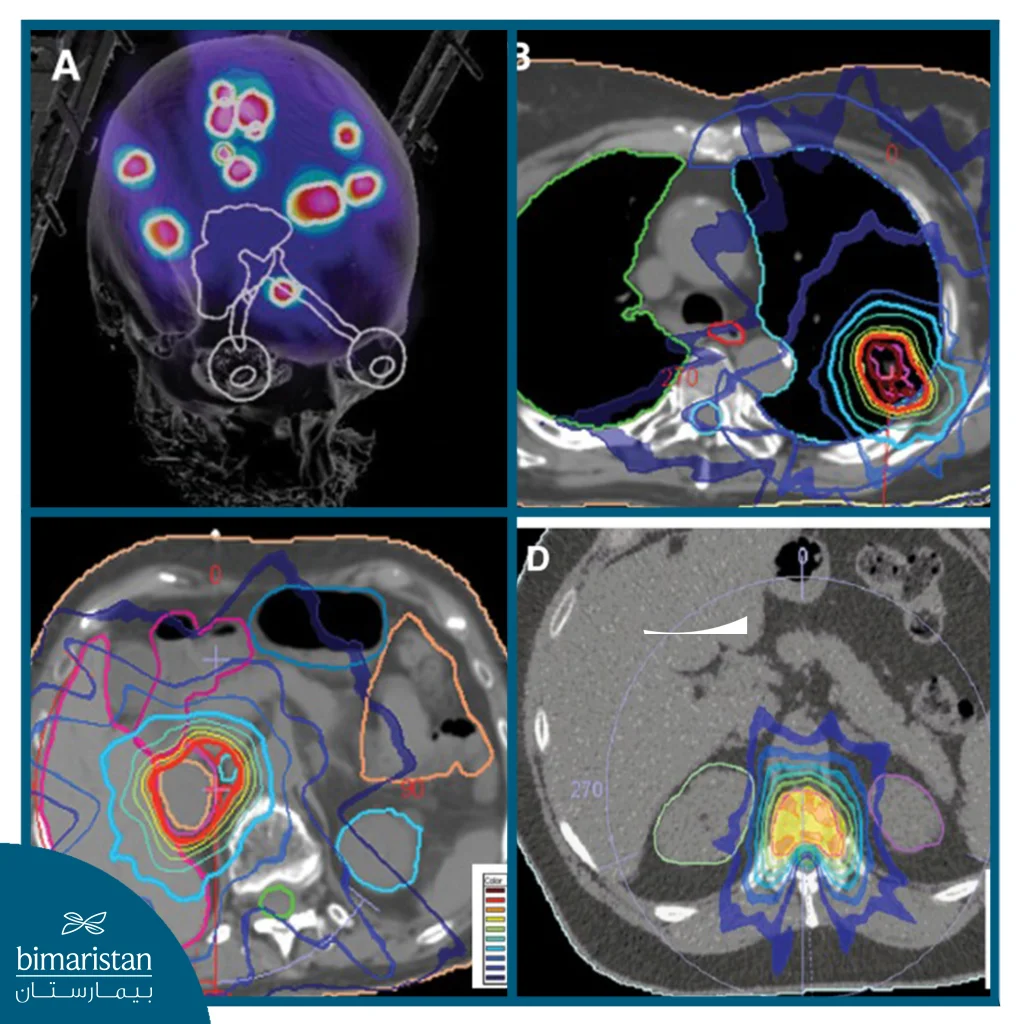

العلاج الإشعاعي التجسيمي للجسم هو علاج للسرطان يستخدم التصوير ثلاثي أو رباعي الأبعاد والحزم الإشعاعية المركزة بدقَّة لإرسال جرعات عالية من الإشعاع إلى المنطقة المقصودة بالعلاج، وينتج عن هذا إلحاق ضرر طفيف للغاية بالأنسجة السليمة المحيطة بالمنطقة، كما هو الحال مع أشكال العلاج الإشعاعي الأخرى، يعمل العلاج بالإشعاع التجسيمي عن طريق إصابة الحمض النووي داخل الخلايا الورمية. حيث يمنع الضرر الناجم عن الإشعاع الخلايا من تكوين مزيد من الخلايا الورمية. ويؤدي ذلك إلى انكماش الأورام.

على عكس العلاج الإشعاعي التقليدي، يوفّر العلاج الإشعاعي التجسيمي الجرعة المثلى من الإشعاع خلال فترة أقصر (أيام وليس أسابيع). حيث يتم توجيه جرعات عالية من الإشعاع إلى الورم نفسه مع تقليل تأثير الإشعاع على الأنسجة والأعضاء السليمة المحيطة لتجنب الضرر.

العلاج الإشعاعي التجسيمي يستهدف الأورام الصغيرة بدقة عالية باستخدام جرعات مركزة من الإشعاع. تُتتميز هذه التقنية بدقتها التي تصل إلى مليمتر واحد أو أقل، ولا تتطلب إجراء عملية جراحية، ويمكن إجراؤها للمرضى الخارجيين. يمكن توصيل الإشعاع باستخدام نظام بدون إطار أو نظام بالإطار التقليدي.وجَّه الأشعة على الورم بحيث تتطابق مع شكله، مما يسمح بتدمير الخلايا السرطانية مع الحفاظ على الأنسجة السليمة المحيطة.

- التخطيط العلاجي بالحاسوب: يستخدم فريق العلاج الصور التي تم الحصول عليها لتصميم خطة ثلاثية الأبعاد دقيقة، تحدد زوايا واتجاهات الأشعة وجرعة الإشعاع المثالية التي تستهدف الورم فقط وتقلل الضرر عن الأنسجة السليمة.

- تنفيذ العلاج: يدور جهاز المسرّع الخطي أو نظام CyberKnife حول المريض بزوايا متعددة، حيث تُوجَّه عدة حزم دقيقة من الإشعاع عالي الطاقة نحو الورم لتتقاطع جميعها في نقطة الهدف بدقة متناهية، مما يؤدي إلى تدمير الخلايا السرطانية دون إلحاق ضرر بالأنسجة السليمة المحيطة.